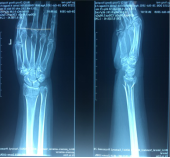

手法整复桡骨远端骨折、踝关节骨折、尺骨骨折、掌骨骨折、指骨骨折、跖骨骨折及肩关节脱位、桡骨小头半脱位等各类骨折脱位十余例,行小夹板固定及石膏托外固定十余例。